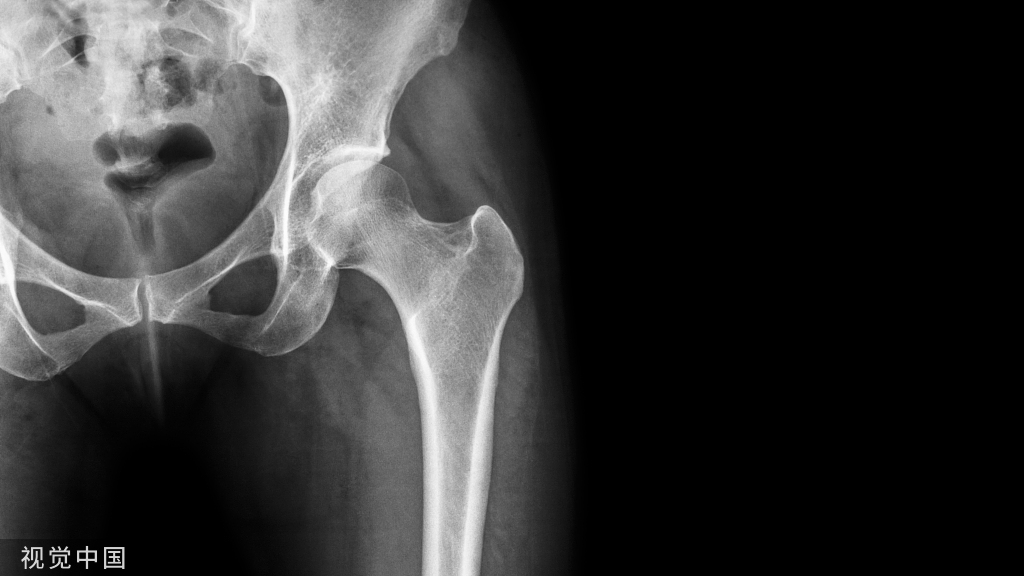

这里有骨质疏松用药的12个「坑」,快来看看你踩过几个?

本文专门就治疗骨质疏松症的一些不合理药物处方进行归纳总结,希望能为骨科医生提供借鉴和参考,进而起到规范医生用药行为和保障患者用药安全的作用。